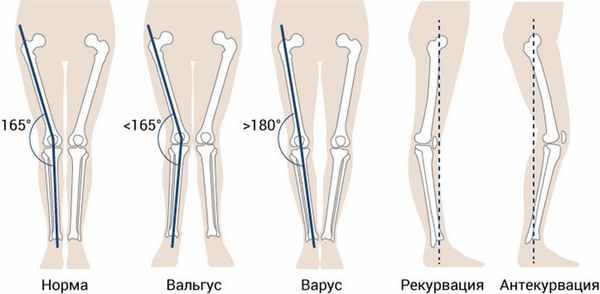

Установочные положения и отклонения костно-суставного аппарата нижней конечности

Варус и вальгус описывают отклонения, наблюдаемые во фронтальной плоскости. Обычно эти термины используются вместе с названием конкретного сустава. Например, «genu varum» — варус колена, «coxa valga» — вальгус тазобедренного сустава, «hallux valgus» — вальгус первого плюснефалангового сустава. Также эти термины могут описывать структурное искривление кости. Например, «варус большеберцовой кости» — её структурное искривление наружу.

Рекурвация / Антекурвация

- Рекурвация — (лат. re назад + curvo гнуть) — отклонение под углом, открытым кпереди

- Атекурвация — (лат. ante вперёд + curvo гнуть) — отклонение под углом, открытым кзади

Рекурвация и антекурвация описывают отклонения, наблюдаемые в сагиттальной плоскости. Чаще всего в практике встречается термин «рекурвация колена» обозначающее переразгибание коленного сустава. Антекурвация отдельной кости может появиться в результате неправильного сращения костей после перелома или впоследствии остеомиелита.

Коленный сустав

Для коленного сустава наиболее характеры вальгус, варус и рекурвация. Считается, что при вальгусной установке колена возникает избыточная нагрузка на латеральный мениск и нагрузка на растяжение большеберцовой коллатеральной связки, а при варусной установке колена возникает избыточная нагрузка на медиальный мениск и нагрузка на растяжение малоберцовой коллатеральной связки. При рекурваци колена возможно перерасяжение задней части суставной капсулы коленного сустава, а также появляется тенденция к ущемлению жирового тела Гоффа нижним краем надколенника.

Рис. 5